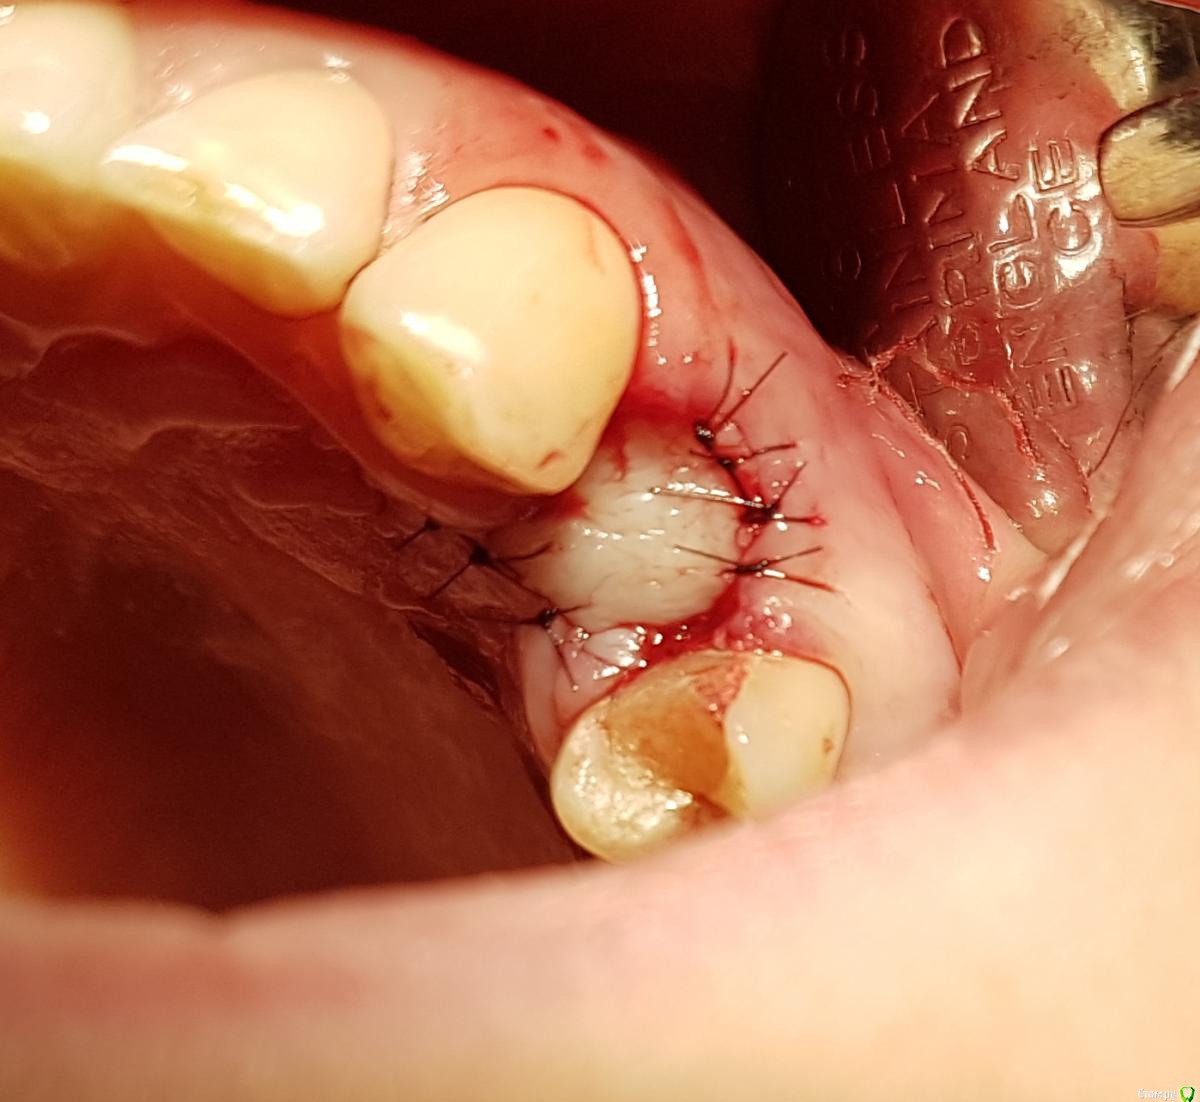

колесников Опубликовано 5 июля, 2019 Автор Поделиться Опубликовано 5 июля, 2019 Ещё раз о ретировалось лоскуте . Из ретромолярной зоны на н/ч перекинут Вестибулярно к 7ке и с неба перекинут Вестибулярно уже для верхней 7ки. Оба случая значительный дефект вестибулярной стенки,одномоментная имплантация,грануляции. Получается хороший стабильный и плотный каркас. 1 зона. 1 Ссылка на комментарий

колесников Опубликовано 10 июля, 2019 Автор Поделиться Опубликовано 10 июля, 2019 Конечно использовал. Там лохань такая,имплант 5х11 только апексом заякорился. Сверху адгезивная повязка. Ссылка на комментарий